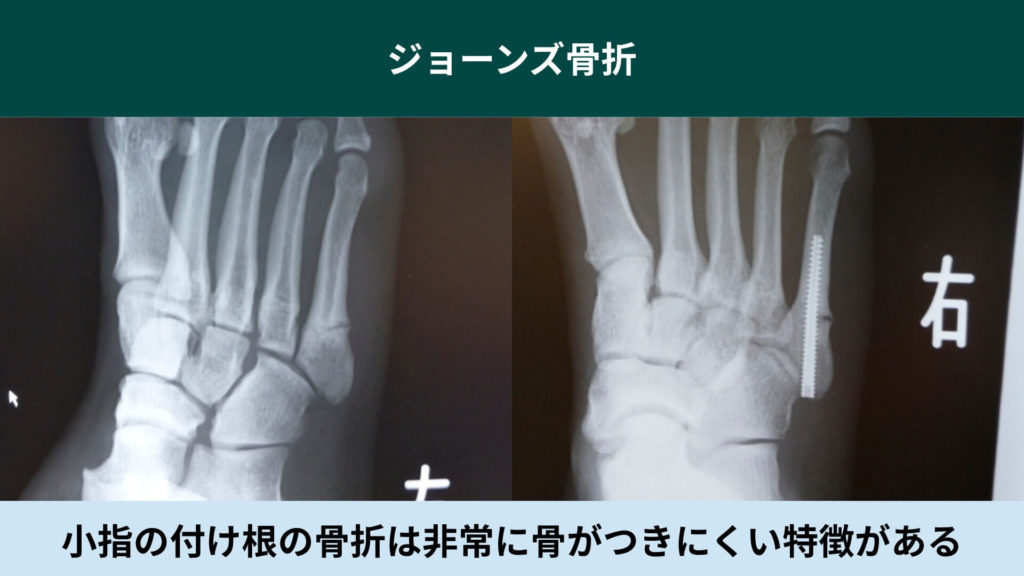

【足】ジョーンズ骨折

足の小指の付け根の骨が骨折してしまうケースをジョーンズ骨折と言います。

短腓骨筋(たんひこつきん)という筋肉が付いている影響で日常生活で歩くだけでも骨が牽引されます。

その影響で通常に固定しても骨がつきにくく、再発してしまう怪我のため手術をすべき怪我です。

保存でも対応はできますが、痛みが軽減すると動きたくなってしまうのが人の心理です。

骨がつきかけた時に動くことで骨が付かなくなってしまうのです。

だから手術をした方が確実でさらに早期復帰できる利点が多い怪我です。